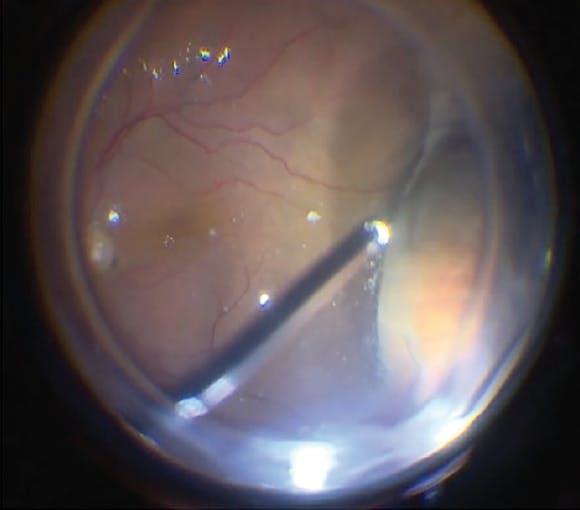

Standard three-port PPV was carried out under local anesthesia. Eyes with coexistent cataract underwent phacoemulsification with IOL implantation. In eyes that underwent limited vitrectomy alone, after three standard ports were created at the pars plana a posterior vitreous detachment (PVD) was induced up to the equator, and limited vitrectomy was completed without disturbing the peripheral cortical vitreous and vitreous base (Figure 3, Video 1).